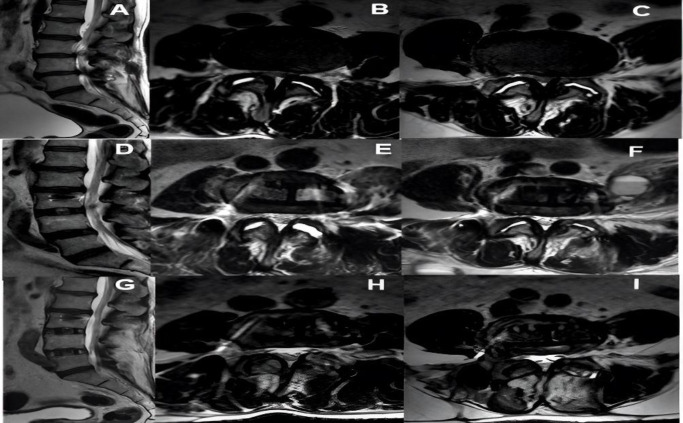

Methods: Imaging changes in patients who underwent indirect lumbar decompression and percutaneous posterior fixation were analyzed with one-year follow-up. Radiographic measurements were performed preoperatively and postoperatively (at one year), and the area of lumbar canal occupation and yellow ligament by nuclear magnetic resonance was compared preoperatively, at 48 hours post-surgery, and at one year. Radiographic measurements included disc height, foraminal height, total lumbar lordosis, and segmental lordosis. The VAS lumbar and lower limb scales and the Oswestry Disability Index (ODI) were used to assess clinical outcomes.

Results: A total of 21 male and 23 female patients underwent indirect decompression at 64 lumbar levels. A significant improvement was observed in the clinical evaluation of all patients' post-surgery (p < 0.001) in all radiographic parameters. There was an immediate increase in the lumbar canal at 48 hours (p < 0.001), which continued to increase at one year post-intervention (p < 0.05). The yellow ligament occupation area decreased at 48 hours (p < 0.001) and continued to decrease until one year (p < 0.01). Four complications were recorded, one of which was a posterior tract infection requiring open decompression.

Conclusion: Indirect decompression for degenerative lumbar disease provided successful clinical outcomes, including indirect expansion of the dural sac at 48 hours post-procedure, with progressive increase in the lumbar canal area at one-year follow-up.